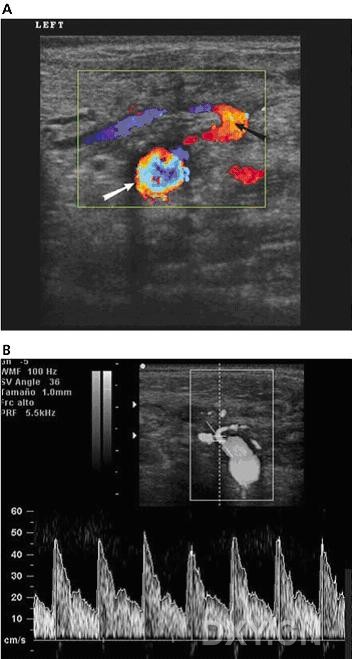

six months after the transplantation, a neck ultrasonographic scan was performed with a high-resolution linear transducer (voluson 730 pro; ge healthcare, waukesha, wi) that showed the transplanted thyroid gland anterior and caudal to the native thyroid (figure 1, a and b). both glands were normal in echogenicity and size. gray scale real-time ultrasonography showed a normal appearance of the inferior transplanted thyroid arteries. color doppler ultrasonography proved vascular perfusion and allowed visualization of the right superior thyroid artery. power doppler ultrasonography showed normal flow within the transplanted thyroid gland (figure 1c). b-mode ultrasonography showed normal dilatation of the carotid artery at the site of the arterial anastomosis (figure 2a); color doppler ultrasonography showed reversal of flow at that point (figure 2b). spectral doppler ultrasonography was performed at the origin of transplanted thyroid arteries and showed peak systolic speeds between 32 and 48 cm/s and end-diastolic velocities between 9 and 13 cm/s with high-resistance waveforms (figure 3b). the evaluation of venous anastomoses was not possible because there were no changes in internal jugular veins allowing differentiation from native thyroid veins. spectral analysis showed both arterial and venous flow within the transplanted thyroid gland, the latter being an indirect sign of patency of the venous anastomoses.

移植手术中将供者气管近端与第一个气管环吻合,将远端在隆凸水平上3cm处吻合。根据手术医生从先前的动物试验模型中发展来的技术,将气管连带甲状腺进行了移植。同时将供者甲状腺下动脉和受者的颈总动脉吻合,将右甲状腺上动脉和受者同侧颈外动脉吻合,甲状腺中静脉与颈内静脉吻合,甲状腺下静脉与无名静脉吻合。2个月后,dsa显示血管(动脉)灌注良好,检查期间静脉相显示不清。病人术后进展平稳,除了有过一次的乳糜胸但也解决了。术后病人拔除了插管,也没出现呼吸困难,予以免疫抑制剂治疗防止排异反应。移植手术后6个月,应用高分辨率的探头行颈部超声检查(ge voluson730 pro),显示移植的甲状腺位于前面,自身甲状腺在后(图1,a和b),两腺体的回声和大小正常。灰阶实时超声扫描显示移植甲状腺下动脉形状正常。彩色多普勒超声证实血管充盈良好,右侧甲状腺上动脉充盈良好。能量多普勒显示移植甲状腺内血流正常(图1,c)。b型超声显示动脉吻合处颈动脉正常扩张(图2,a)。彩色多普勒显示此处血流反转(图2,b)。频谱多普勒超声显示移植甲状腺动脉起始点的收缩期峰值流速在32-48cm/s,舒张末期流速在9-13cm/s,呈高阻力波形(图3,b)。由于无法区分自身甲状腺静脉和颈内静脉,因此静脉吻合处的检查不能评估。频谱多普勒显示移植甲状腺内的动脉和静脉分布正常。后者间接表明了静脉吻合处是开放的。

图1 a, b超轴切面显示18岁的患者器官移植后的4个甲状腺叶片。移植腺体(黑箭头)位于自身甲状腺(白箭头)的前方。两者回声正常。b,左侧甲状腺叶片b超纵切面显示移植甲状腺(黑箭头)在前,自身甲状腺(白箭头)位于后方。c,能量多普勒显示甲状腺实质内血管供应正常(左侧自身腺体和移植甲状腺叶片分别用白色和黑色箭头表示)。